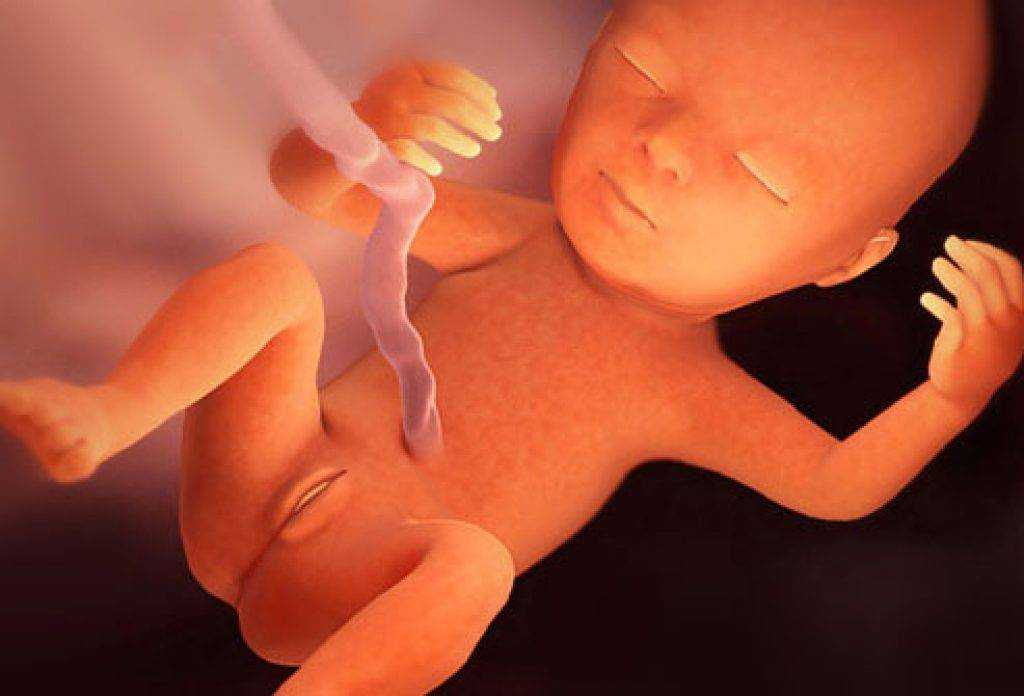

Фотография Плода В Животе

Фотография Плода В Животе 113 фотографий